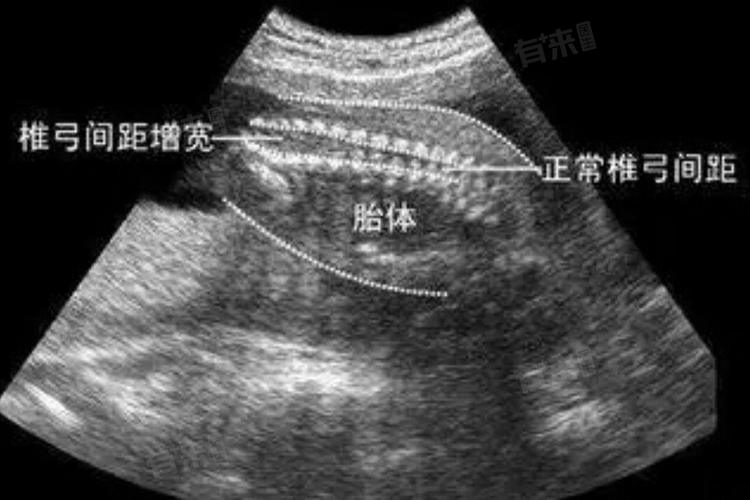

- 大排畸检查可以观察到胎儿的头部、面部、颈部、胸部、腹部、四肢等多个部位,以发现如无脑畸形、严重脑膨出、严重开放性脊柱裂等重大畸形。这项检查对于及时发现问题、评估预后具有重要意义,有助于减少严重出生缺陷的发生。